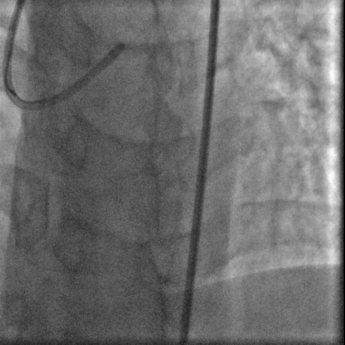

经右股动脉(8F),送EBU 3. 5指引导管指引导管至左冠开口。Sionblue导丝至LCX保护,Finecross 130到达LCX远端待命。Sionblue引导Corsair 135cm微导管进入LAD。近段纤维帽坚硬(伴钙化随后IVUS证实)尝试使用Gaia1st进入前次假腔,导丝升级Gaia 3rd谨慎前进入间隔支S1,推送corsair进入S1交换KDLC,Pilot 200导丝平行进入LAD真腔。Corsair交换Sionblue到LAD远端。IVUS证实全程真腔,闭塞段以纤维为主。植入支架完成血运重建。

Pilot200进入真腔

结果

IVUS影像提示导丝位于闭塞段斑块内,斑块以纤维斑块为主。